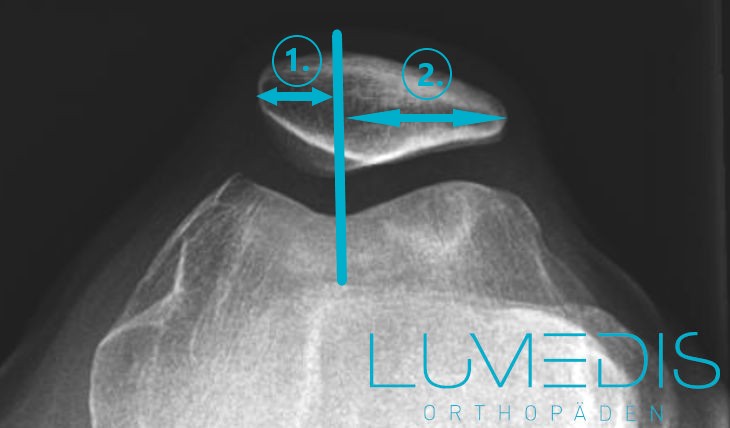

Röntgenbild Defilee der Kniescheibe bei Patellalateralisation

Das Gleitlager (Trochlea) wird symmetrisch geteilt.

Röntgenbilder werden vor allem dann angewandt, wenn man knöcherne Strukturen sehen und beurteilen will. Zur Diagnostik einer Jägerhutpatella wird die sogenannte Defilee Aufnahme durchgeführt. Hierfür liegt der Patient auf dem Rücken oder sitzt, ein Polster wird unter seine Kniekehle gelegt, der Beugungswinkel kann hierdurch in unterschiedlichen Graden verändert werden, während die Röntgenaufnahmen durchgeführt werden. Durch diese Position kann man sehr gut Veränderungen an der Unterseite der Patella sehen und eine entsprechende Veränderung im Sinne einer Jägerhutpatella beurteilen.